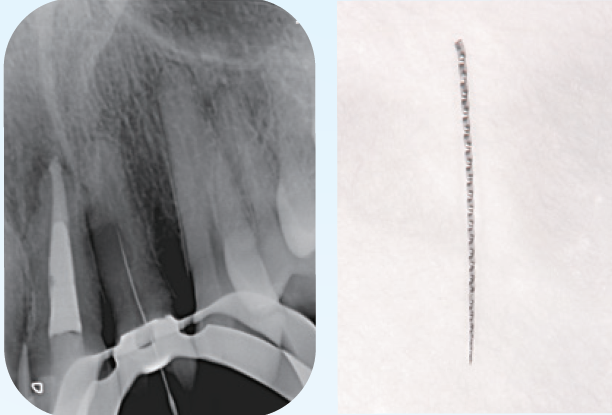

「臨床症例3」2022年9月16日に上顎前歯部腫脹と鈍痛を主訴に紹介元の歯科医院を受診

●年齢 40代 男性

難治性歯内療法疾患と診断を受け、当院を紹介される。同年10月19日当院を受診。問診時、10代の時に前歯部を強打し歯科医院を受診するも経過観察のまま放置していたとのことで、上顎左側中切歯の根尖部が外部吸収様の形態が確認でき、根尖孔もかなり開いていることが予測できた。CBCTでは唇側皮質骨は開窓し、根尖病変は中切歯、側切歯の根尖部を含む広範囲に広がっていることが確認できる。治療においては根尖孔のゲージングで#100とし、作業長の1ミリアンダーに止まるリーマー#120で抵抗形態を付与し、MTA製剤の根尖外への溢出を極力抑えるように努めて根尖部の閉鎖を行った。

その次に、上顎左側側切歯の感染根管処置を行った。側切歯は中切歯とは違い、狭窄が進行し穿通障害歯を呈していた。穿通し作業長を確認し、根管充填を行った。術後3ヶ月、1年の状態は治癒傾向が継続しており、臨床症状も無い。外科的アプローチを回避できる結果となった。

臨床症例3 その1

①初診時(2022/10/19)

左上1、2番の根尖部を含む大きさの根尖病変が認められる

左上1は根尖部は外部吸収が認められる

②左上1番 EMR時レントゲン像

根根尖孔径は#100に相当した

③MTA製剤を用いて根管充填を行なった

作業長1ミリアンダーに#120のリーマーにて抵抗形態を付与しMTA製剤が根尖外に多量に溢出しないように努めた

④根管口まではガッタパーチャとMTAシーラーを用いて充填した